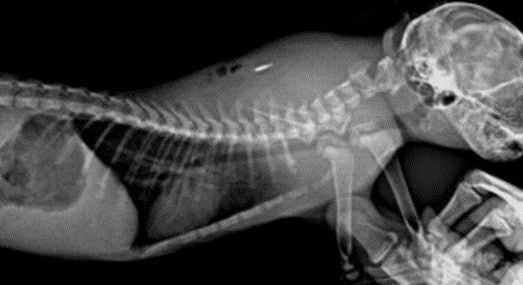

Обязательно были проведены диагностические мероприятия, в частности рентгенодиагностика и анализы крови, где выявлены признаки воспалительного процесса в месте чипа (абсцесс/флегмона).